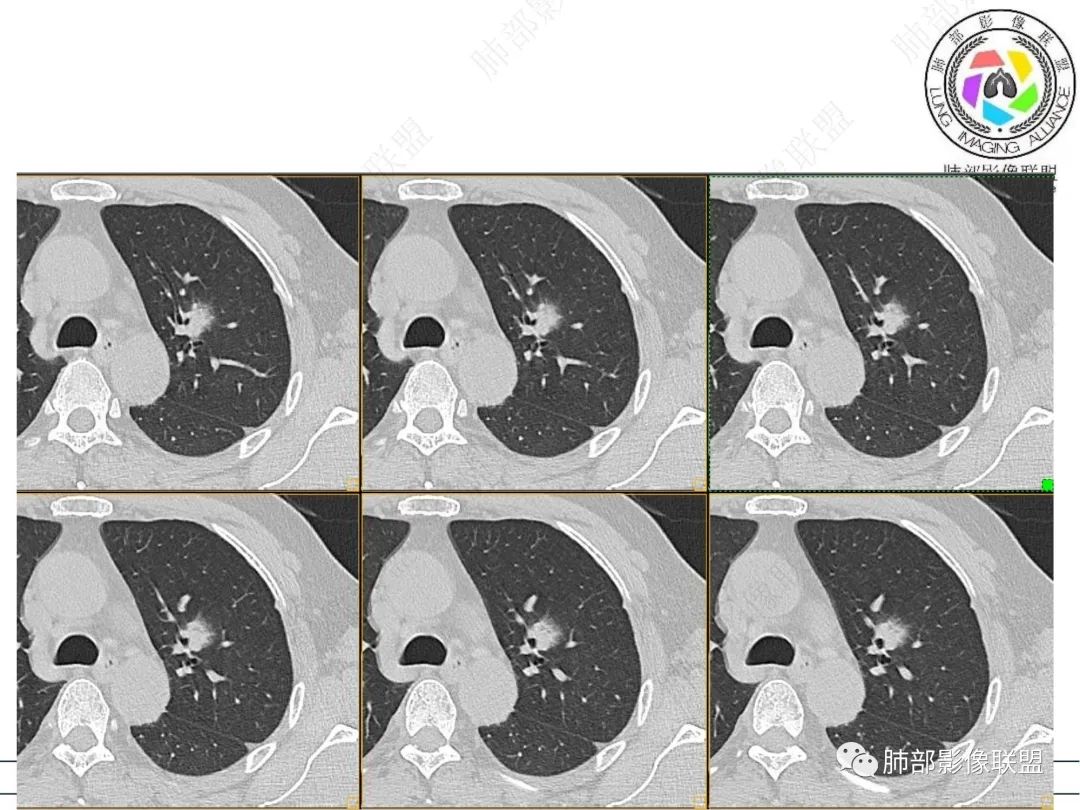

男性,肺结节3年,发现逐渐增大,影像表现,左肺舌段结节,边缘可见磨玻璃密度影,内部走形下舌段支气管变窄,增强呈持续强化,首先考虑肺腺癌,鉴别炎性肉芽肿,真菌/隐球菌。

中老年男性,发现结节,影像表现,左肺上叶结节,实性部分有膨胀性生长,边缘可见磨玻璃影,似清晰似不清晰,病灶与支气管关系密切,部分支气管似狭窄及僵硬,增强病灶强化明显,考虑腺癌(粘液性腺癌)鉴别炎性肉芽肿。

左肺上叶尖段支气管旁结节伴磨玻璃影,磨玻璃影边缘模糊,支气管走形正常,病变无明显分叶及毛刺,收缩不明显,增强呈延迟高强化。先考虑炎性肉芽肿。肿瘤待排。

左肺上叶支气管旁结节伴磨玻璃影,磨玻璃边缘略模糊,沿支气管走行,明显不均匀延迟强化,3年逐渐增大,考虑腺癌,鉴别淋巴增殖病变,炎性肉芽肿

左肺上叶尖后段结节,围绕支气管生长,周围磨玻璃影,边缘似清不清的感觉,三年病变明显增大,增强呈延迟高强化。考虑腺癌,高强化的腺癌不少见,鉴别炎性肉芽肿

361度:

2、病灶以实性密度为主,前、外侧蔓延,GGO部分边界清楚,部分欠清

支气管未见受明显侵犯,未见阻塞,壁增厚,狭窄或扩张。

软组织+重建;病灶实性部分不是类圆形,密度相对均匀柔和。

肺门区病灶与支气管关系不密切,强化显著、磨玻璃晕等等容易想到的是肺腺癌。而不首先考虑与支气管密切相关恶性肿瘤,如鳞癌、类癌、粘液表皮样癌等等。